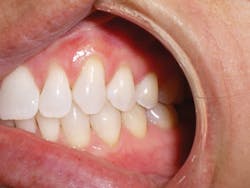

Four weeks later, Evin began his clear aligner treatment (see Figure 1). He was seen for follow-up clear aligner visits at six-week intervals until his treatment was completed. During his clear aligner treatment, Evin maintained three-month recalls with the hygienist. His home care was excellent, in part due to the benefit of aligners being removable.

Figure 1

Evin is a perfect example of this. He always had beautiful teeth. Dr. Miraglia could see that they were just in the wrong place! Insufficient space, as a result of improper arch forms is the cause of crowding, not "crooked" teeth (see Figure 1).